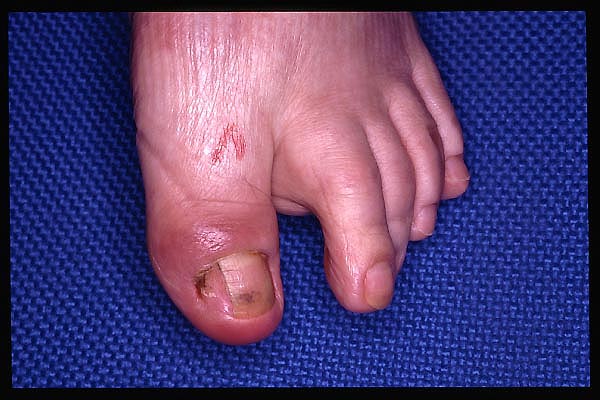

Trauma directo contra dedo. sin fracturas.